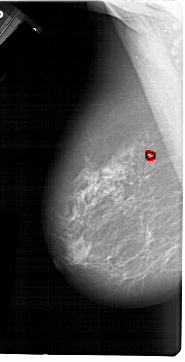

A_1214_1.LEFT_CC

LEFT_CC LINES 6181 PIXELS_PER_LINE 3316 BITS_PER_PIXEL 12 RESOLUTION 43.5 OVERLAY

FILE: A_1214_1.LEFT_MLO.OVERLAY

TOTAL_ABNORMALITIES 1

ABNORMALITY 1

LESION_TYPE CALCIFICATION TYPE PLEOMORPHIC DISTRIBUTION CLUSTERED

ASSESSMENT 4

SUBTLETY 4

PATHOLOGY MALIGNANT

TOTAL_OUTLINES 1